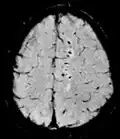

| Susceptibility-weighted | SWI | Spoiled gradient recalled echo (GRE), fully flow compensated, long echo time, combines phase image with magnitude image[12] | Detecting small amounts of hemorrhage (diffuse axonal injury pictured) or calcium.[12] |

Susceptibility-weighted imaging (SWI) is a new type of contrast in MRI different from spin density, T1, or T2 imaging. This method exploits the susceptibility differences between tissues and uses a fully velocity-compensated, three-dimensional, RF-spoiled, high-resolution, 3D-gradient echo scan. This special data acquisition and image processing produces an enhanced contrast magnitude image very sensitive to venous blood, hemorrhage and iron storage. It is used to enhance the detection and diagnosis of tumors, vascular and neurovascular diseases (stroke and hemorrhage), multiple sclerosis,[52] Alzheimer's, and also detects traumatic brain injuries that may not be diagnosed using other methods.[53]